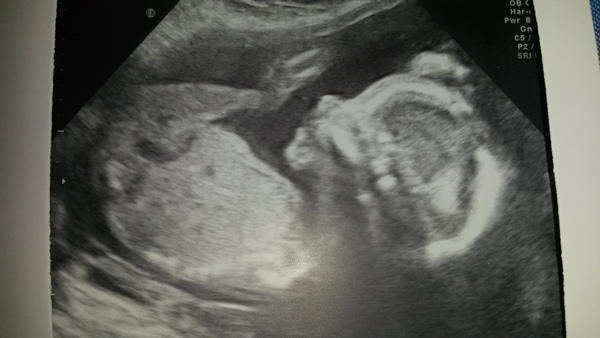

All looking ok at the 20 week scan Smile Stayed team yellow.

Scan all good. 13+4. Had to wait a g e s ...

What a cute scan gr33dy, such a cute little button nose!